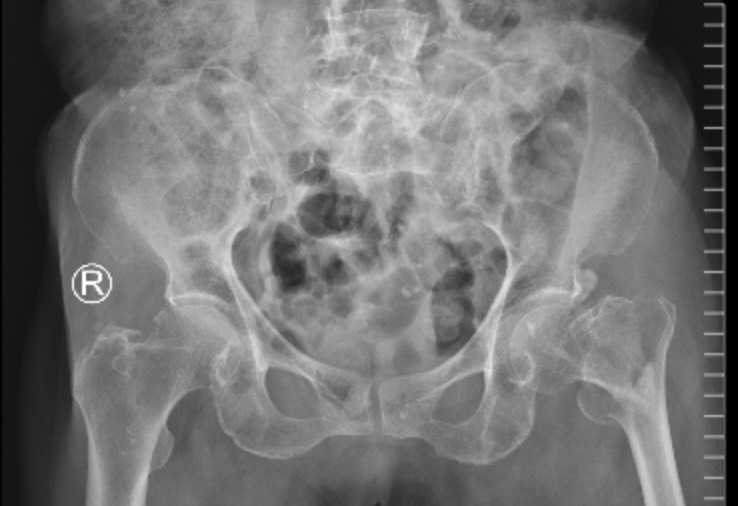

Hình cảnh xương đùi bệnh nhân N. sau phẫu thuật

Sau hơn một giờ thực hiện kỹ thuật, ca phẫu thuật rất thành công. Sau 3 ngày phẫu thuật, bệnh nhân hồi phục tốt, tập vận động chân tốt, sức khỏe ổn định và bệnh nhân đã được xuất viện sau 10 ngày điều trị.